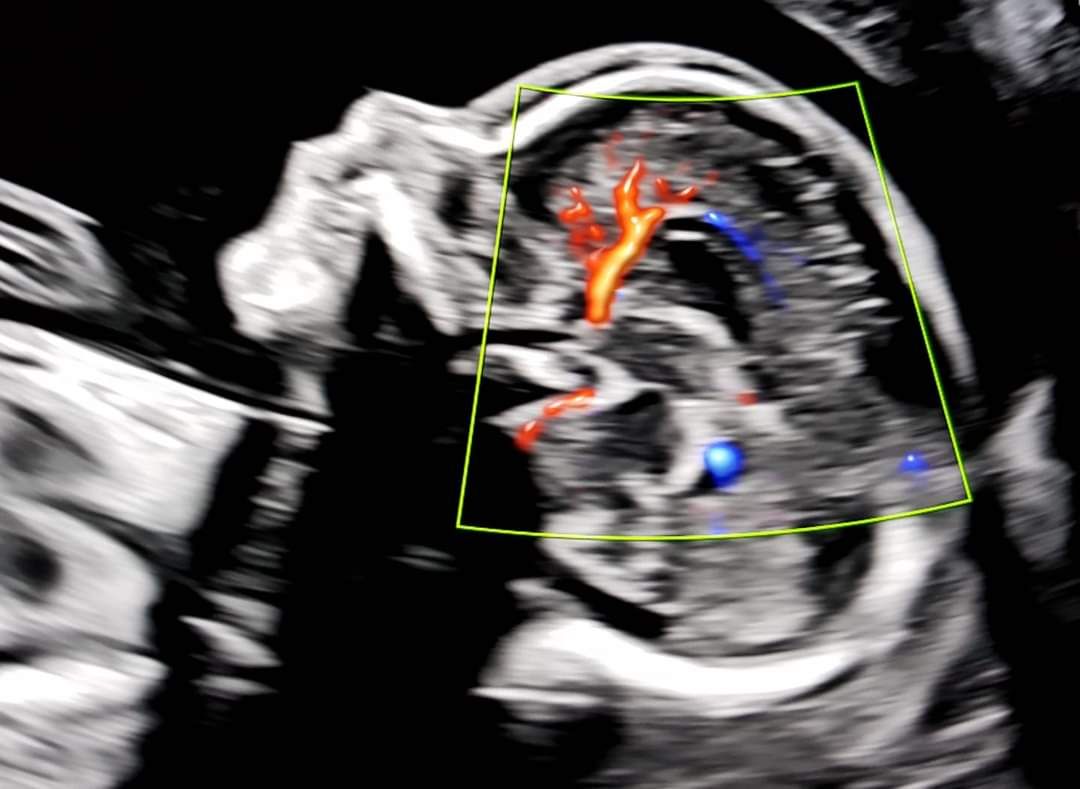

Foto e video